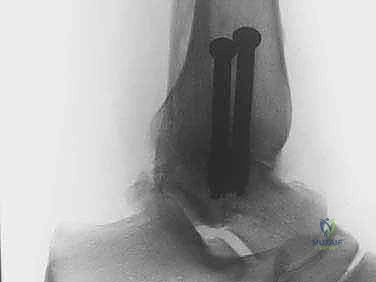

الخطوة الخامسة: التثبيت المحكم (Rigid Fixation)

بمجرد تحضير العظام، يتم وضع القدم في الوضعية الوظيفية المثالية للمشي (عادة بزاوية 90 درجة مع الساق). يتم إدخال براغي معدنية قوية (عادة من التيتانيوم) عبر الجلد وبمساعدة الأشعة السينية الفلورية (C-arm) لضغط العظمتين معاً وتثبيتهما بقوة. هذا الضغط المحكم يمنع أي حركة ويسمح للعظام بالالتحام.